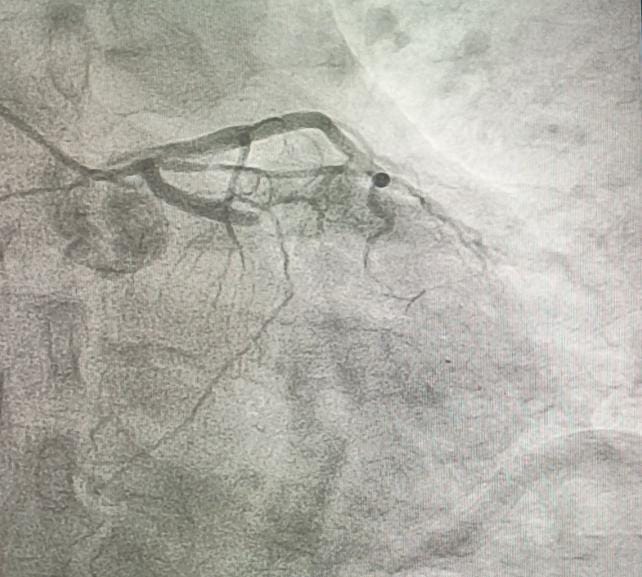

Coronary angiography revealed total occlusion of the proximal LCx and a sub totally occluded RCA with thrombus.

Both RCA and LCx were considered as the culprit lesion. We decided to addressed the lesion in RCA first, since the flow is still TIMI III. RCA was engaged with 6F JR guiding catheter. Run through wire was advanced distally to RCA. After pre dilatation with NC balloon 3.5 / 18 mm the thrombus disappeared. A 3.5 / 22 mm stent was implanted in RCA at 18 atm. Post dilatation with stent balloon at maximum pressure 20 atm. Final angiogram showed TIMI 3 flow. Then we intervene the LCx. We used BL guiding catheter to engage the LCx. Run through NS floppy wire was advanced to distal LCx. Coronary angiogram showed good contrast flow to distal LCx. Pre dilatation at proximal LCx with NC balloon 3.5 / 18 mm at 18 atm. DES was implanted at LCx at 20 atm. We did post dilatation at LCx with NC balloon up to 24 atm. Final angiogram showed TIMI III flow.